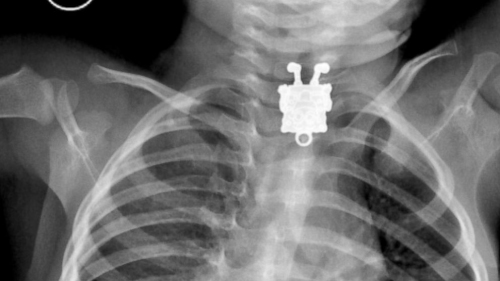

X光片显示出一个“海绵宝宝”。

中新网1月29日电 据外媒报道,沙特一名医生近日在为一名孩子拍摄X光片时,惊讶地发现孩子体内有一个“海绵宝宝”饰品。

据报道,这名医生叫安吉利,他是阿卜杜拉阿齐兹国王大学医院的放射科医生。他告诉媒体称,在X光片里能清晰看到孩子吞下的“海绵宝宝”卡通形象。

安吉利医生说,从X光片里看,这个“海绵宝宝”像是一个吊坠,上面有可以挂绳子的地方。

“我觉得也可能是个别针,”安吉利医生说,当他第一次看到X光片的时候吓坏了,一个“海绵宝宝”笑脸相迎的样子让他相当震惊,“而且拍摄角度和朝向实在是很完美。”